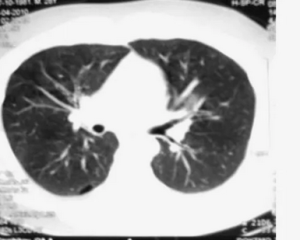

Проведено ретроспективно - проспективное когортное исследование на базе отдела фтизиатрии ФГБНУ ЦНИИТ с 2020 по 2024 год. Всего в исследование было включено 368 больных туберкулезом легких. Больные были распределены на две группы: 1 группа - больные курящие (194 человека), 2 группа - больные некурящие (174 человека). Критериями включения в исследование являлись: возраст 18 лет и старше, подтвержденный диагноз туберкулеза легких, больные курящие и некурящие. Критериями невключения являлись: возрасте менее 18 лет, неподтвержденный диагноз туберкулеза легких, наличие ВИЧ - инфекции и онкологических заболеваний. Проведен анализ половой и возрастной структуры больных, а также распространенности туберкулезного процесса и клинических форм туберкулеза. Была изучена частота проведения хирургического этапа лечения как среди курящих, так и некурящих больных, а также структура объёма хирургического вмешательства. Проведение хирургического лечения осуществлялось через 2, 4 и 6 месяцев противотуберкулезного лечения на стационарном этапе.

Анализ распространенности различных форм туберкулезного процесса выявил преобладание распространенных форм в группе курильщиков по сравнению с группой некурящих: 171 человек (88,1%) и 129 человек (74,1%) соответственно, p<0,001. Также были получены значимые различия в структуре объёма поражения, которые представлены в таблице 2.

Как видно из таблицы 2, в группе курящих по сравнению с некурящими больными преобладали патологические процессы, вовлекающие все легкое, p=0,002. При этом, объёмы поражения, вовлекающие 1 - 2 сегмента легочной ткани, преобладали в группе некурящих, p<0,001.